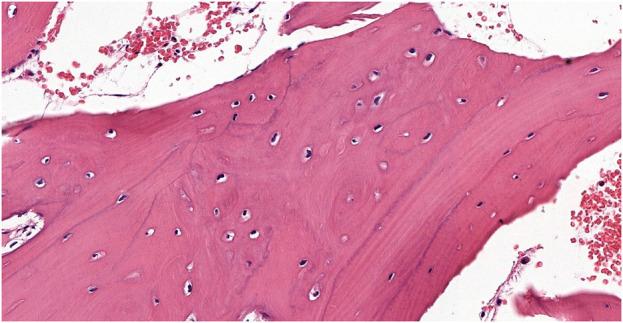

Gardner syndrome is a rare genetic cancer predisposition disorder characterized by intestinal polyposis, multiple osteomas, and soft and hard tissue tumors. Dental anomalies are present in approximately 30%-70% of patients with Gardner syndrome and can be discovered during routine dental examinations. However, sometimes the diagnosis is challenging due to the high clinical variability and incomplete clinical picture. Herein, we report a family with various dental and bone anomalies, in which the definitive diagnosis was established with the help of a comprehensive genetic analysis based on state-of-the-art next-generation sequencing technology. A 17-year-old female index patient presented with dental (caries, impacted, retained and anteriorly located teeth) and atypical bone anomalies not resembling Gardner syndrome. She was first referred to our Genetic Counselling Unit at the age of 11 due to an atypical bone abnormality identified by a panoramic X-ray. Tooth 3.6 was surgically removed and the histopathology report revealed a Paget's disease-like bone metabolic disorder with mixed osteoblastic and osteoclastic activity of the mandible. A small lumbar subcutaneous tumor was discovered by physical examination. Ultrasound examination of the tumor raised the possibility of a soft tissue propagation of chondromatosis. Her sister, 2 years younger at the age of 14, had some benign tumors (multiple exostoses, odontomas, epidermoid cysts) and impacted teeth. Their mother had also skeletal symptoms. Her lower teeth did not develop, the 9th-10th ribs were fused, and she complained of intermittent jaw pain. A cranial CT scan showed fibrous dysplasia on the cranial bones. Whole exome sequencing identified a heterozygous pathogenic nonsense mutation (c.4700C>G; p.Ser1567*) in the gene in the index patient's DNA. Targeted sequencing revealed the same variant in the DNA of the other affected family members (the sister and the mother). Early diagnosis of this rare, genetically determined syndrome is very important, because of the potentially high malignant transformation of intestinal polyps. Dentists should be familiar with the typical maxillofacial features of this disorder, to be able to refer patients to genetic counseling. Dental anomalies often precede the intestinal polyposis and facilitate the early diagnosis, thereby increasing the patients' chances of survival. Genetic analysis may be necessary in patients with atypical phenotypic signs.